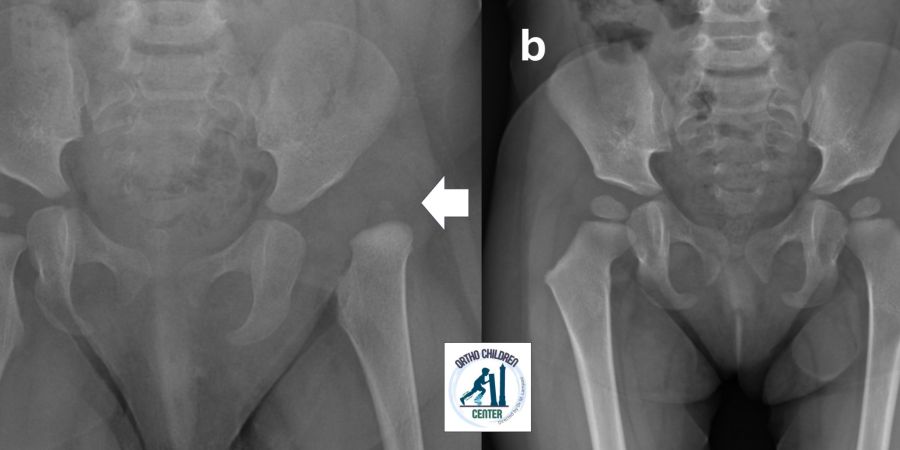

📌 Bimba di 6 anni con emiparesi sinistra (Paralisi Cerebrale Infantile), piede sinistro equino-varo. Già sottoposta a ripetute inoculazioni di tossina botulinica. Deformità progressiva

📌 Sottoposta ad intervento correttivo con ottimo risultato, mantenuto a distanza di anni